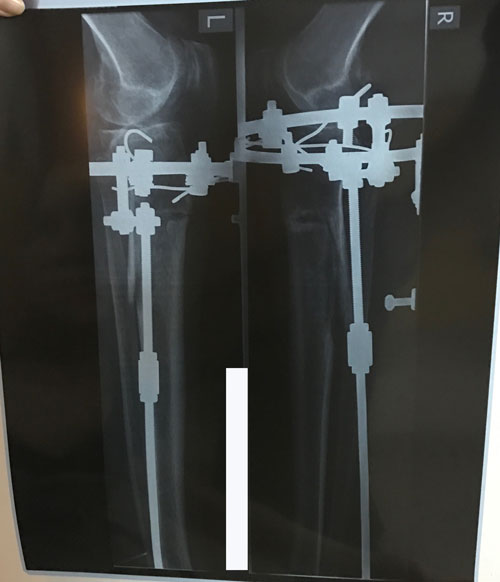

Исходник - 60 лет.

Дата операции 23.05.2017г.

В процессе круток

Рентген и ото ножек в 60 дней.

Срастаетесь, как молодые девчонки

Спасибо за дисциплинированность! Всегда высылаете всё во время.